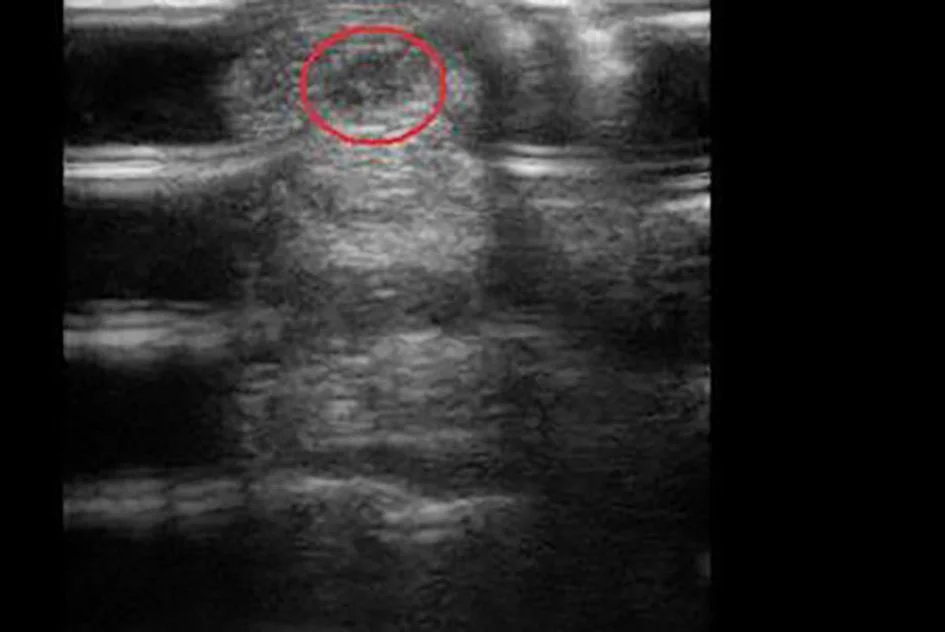

Services Include: Lameness Consultations, Pre-purchase Exams, Shoeing Advice, Tendon Ultrasound Scans, Wound Treatment and Bandaging. Radiography, Manual Dental Floating for Performance Horses.